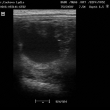

ultrasonografické vyšetření klisny

Preovulační folikul